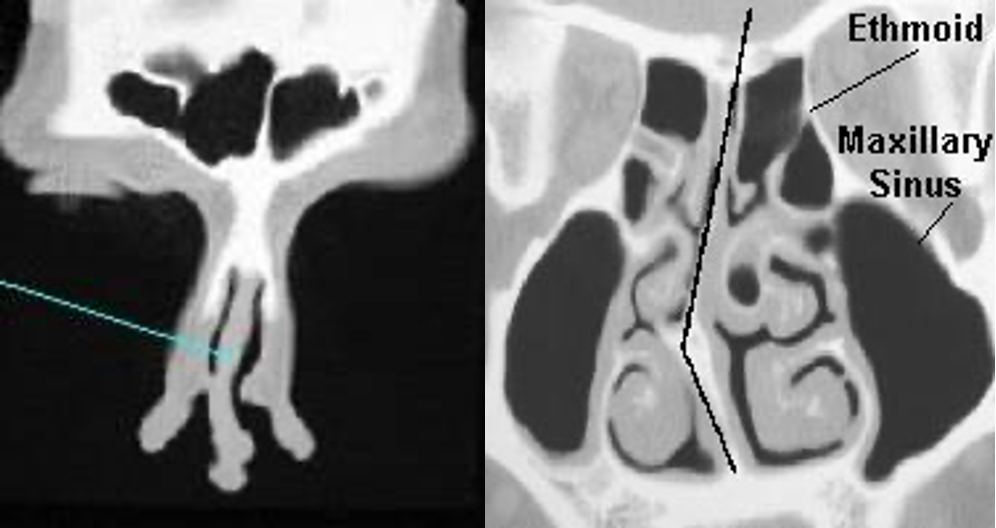

Radiology

- Unnecessary in most cases

Septal

Deviation